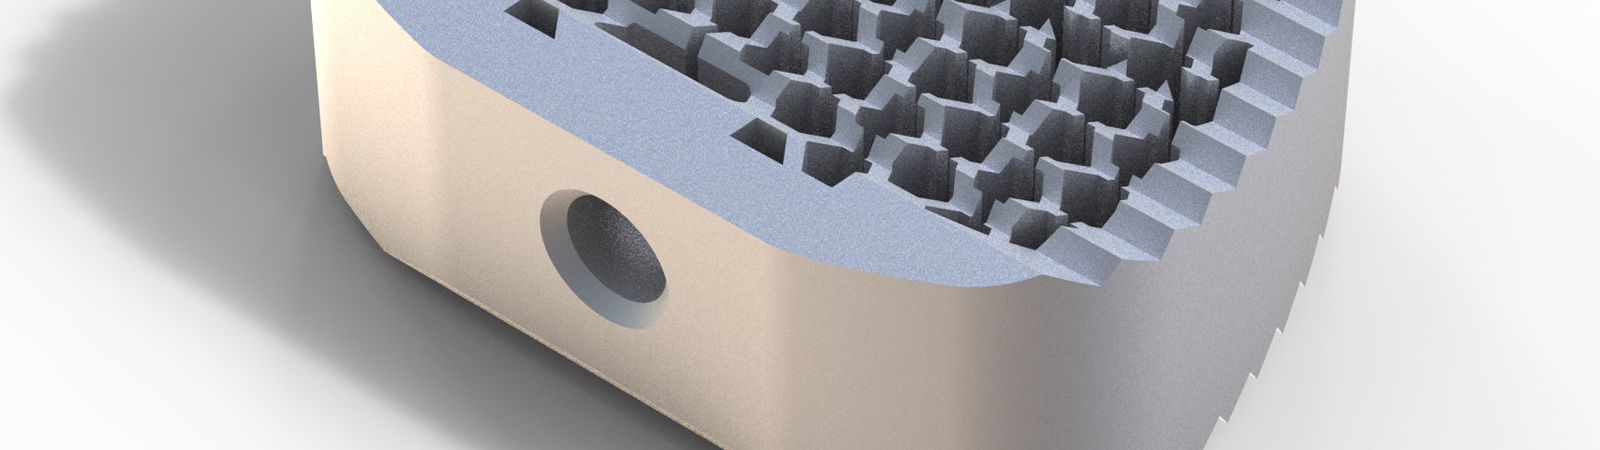

Alle Modelle nun mit der patentierten hygroskopischen Struktur. Diese Kapillarwirkung beeinflusst das Einwachsverhalten positiv ohne Verwendung von autologem Knochen.

HYGROCervicaler Cage aus Titan

Hygro ist ein Unikat auf dem Markt. Wie der Name schon sagt werden durch eine spezielle Anordnung der Lamellen im Inneren des Cages optimale hygroskopische Eigenschaften erziehlt. Eine Fusion wird hierbei erzielt ohne den Cage mit autologem Knochen oder Knochenersatzmaterial zu befüllen.